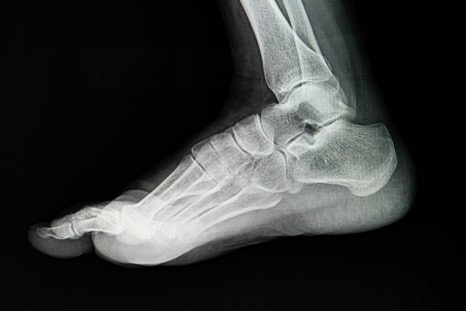

족저근막은 발뒤꿈치 뼈(종골)에서 시작하여 발가락 기저 부위까지 부채꼴 모양으로 넓게 퍼져 있는 강하고 두꺼운 섬유띠입니다. 이 조직은 우리 발의 아치 구조를 유지하는 핵심적인 역할을 하며, 보행 시 지면으로부터 오는 충격을 완화해 주는 스프링과 같은 기능을 담당하죠.

이 두꺼운 막에 미세한 손상이 반복적으로 가해지면 근막을 구성하는 콜라겐의 변성이 일어나고 염증이 생기게 되는데, 이를 족저근막염이라고 불러요.